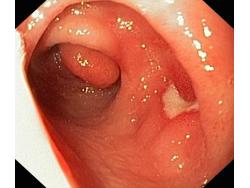

Wrzód trawienny